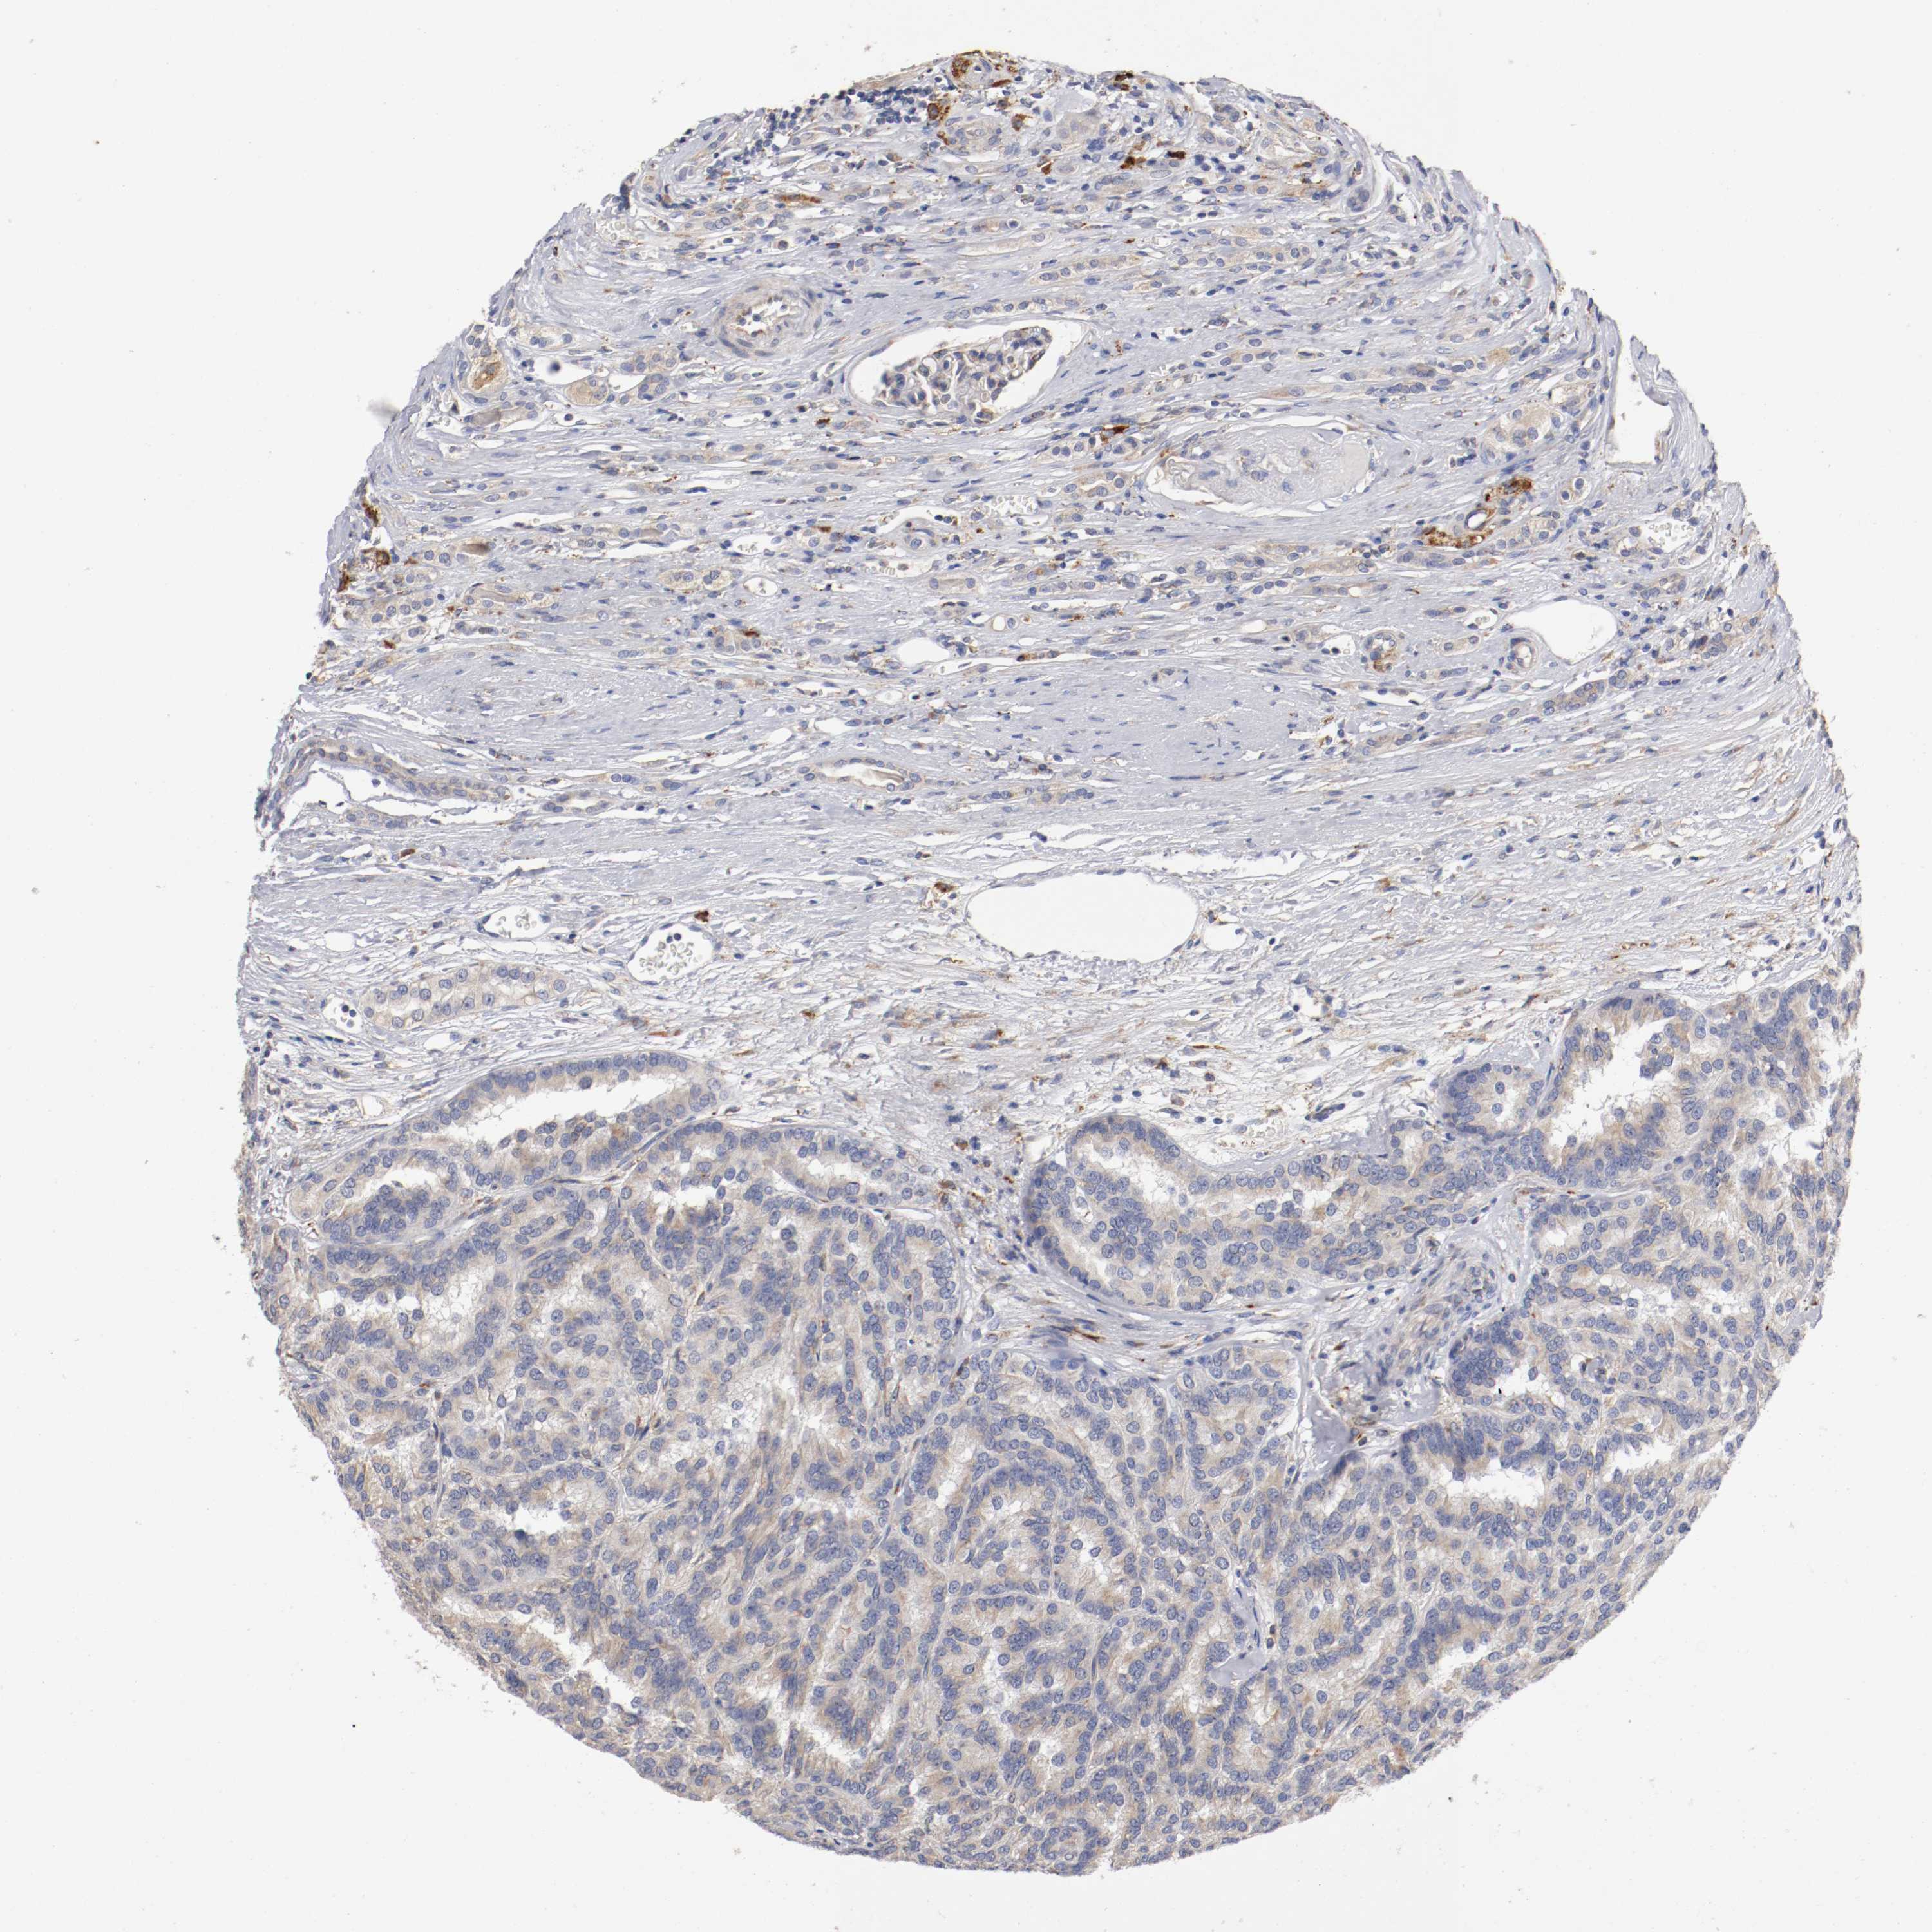

KIDNEY RENAL CLEAR CELL CARCINOMA (VALIDATION) - Interactive survival scatter ploti

The Survival Scatter plot shows the clinical status (i.e. dead or alive) for all individuals in the patient cohort, based on the same data that underlies the corresponding Kaplan-Meier plots. Patients that are alive at last time for follow-up are shown in blue and patients who have died during the study are shown in red.

The x-axis shows the expression levels (FPKM) of the investigated gene in the tumor tissue at the time of diagnosis. The y-axis shows the follow-up time after diagnosis (years). Both axes are complimented with kernel density curves demonstrating the data density over the axes. The top density plot shows the expression levels (FPKM) distribution among dead (red) and alive patients (blue). The right density plot shows the data density of the survived years of dead patients with high and low expression levels respectively, stratified using the cutoff indicated by the vertical dashed line through the Survival Scatter plot. This cutoff is automatically defined based on the FPKM cutoff that minimizes the p-score. The cutoff can be changed by dragging the vertical line or by entering a cutoff value in the square labeled "Current cut-off".

Under the Survival Scatter plot the p-score landscape (black curve; left axis) is shown together with dead median separation (red curve; right axis). Dead median separation is the difference in median mRNA expression between patients who have died with high and low expression, respectively. It is calculated as follows: median FPKM expression of dead patients with high expression - median FPKM expression of dead patients with low expression. This is intended to aid the user in visually exploring custom cutoffs and the associated p-scores and dead median separation.

Individual patient data is displayed and can be filtered by clicking on one or more of the category buttons on the top of the page. Categories describing expression level and patient information include: high, low, alive, dead, female, male and tumor stages. The scale of the x-axis can be toggled between linear and log-scale by clicking on the "x log" button. Mouse-over function shows TCGA ID, patient information and mRNA expression (FPKM) for each patient.

& Survival analysisi

Kaplan-Meier plots summarize results from analysis of correlation between mRNA expression level and patient survival. Patients were divided based on level of expression into one of the two groups "low" (under cut off) or "high" (over cut off). X-axis shows time for survival (years) and y-axis shows the probability of survival, where 1.0 corresponds to 100 percent.

TRAF2 is not prognostic in Kidney Renal Clear Cell Carcinoma (validation)

Best expression cut offi

Based on the FPKM value of each gene, patients were classified into two groups and association between prognosis (survival) and gene expression (FPKM) was examined. The best expression cut-off refers the FPKM value that yields maximal difference with regard to survival between the two groups at the lowest log-rank P-value. Best expression cut-off was selected based on survival analysis .

When clicking on this number, the vertical dashed line indicating cut-off, the interactive survival plot, and the Kaplan-Meier curve will be adjusted to show results based on the best expression cut-off.

: 13.68

Median expressioni

Median expression refers to the median FPKM value calculated based on the gene expression (FPKM) data from all patients in this dataset. When clicking on this number, the vertical dashed line indicating cut-off, the interactive survival plot, and the Kaplan-Meier curve will be adjusted to show results based on the median expression.

: N/A

Median follow up timei

Median follow up time refers to the median time (years) after diagnosis with this type of cancer, based on clinical data from all patients in this dataset.

P scorei

Log-rank P value for Kaplan-Meier plot showing results from analysis of correlation between mRNA expression level and patient survival.

N/A

5-year survival highi

5-year survival for patients with higher expression than the expression cutoff.

For melanoma and glioma, 3-year survival is shown.

5-year survival lowi

5-year survival for patients with lower expression than the expression cutoff.

TCGA RNA samplesi

RNA-seq data is reported as average FPKM (number Fragments Per Kilobase of exon per Million reads), generated by the The Cancer Genome Atlas (TCGA) .

Normal distribution across the dataset is visualized with box plots, shown as median and 25th and 75th percentiles. Points are displayed as outliers if they are above or below 1.5 times the interquartile range. FPKM values of the individual samples are presented next to the box plot.

Average pTPM 17.4

Number of samples 100